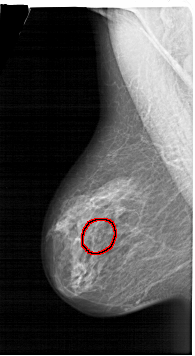

A_1455_1.RIGHT_CC

RIGHT_CC LINES 6466 PIXELS_PER_LINE 3601 BITS_PER_PIXEL 12 RESOLUTION 43.5 NON_OVERLAY

FILE: A_1455_1.LEFT_MLO.OVERLAY

TOTAL_ABNORMALITIES 1

ABNORMALITY 1

LESION_TYPE CALCIFICATION TYPE PLEOMORPHIC DISTRIBUTION CLUSTERED

ASSESSMENT 4

SUBTLETY 3

PATHOLOGY BENIGN

TOTAL_OUTLINES 1